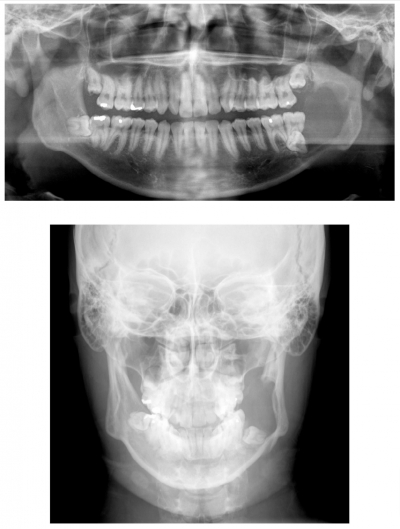

24歳の男性。下顎左側大臼歯部の腫脹を主訴として来院した。同部に境界明瞭な無痛性の腫脹を認める。初診時のエックス線写真、CT及び MRI T1強調像と脂肪抑制T2強調像を別に示す。